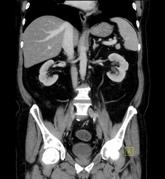

Je nach Fragestellung müssen Sie vor der Untersuchung Kontrastmittel trinken, damit der Magen- Darm- Bereich besser dargestellt werden kann. Die Kontrastmittelmenge beträgt meist 1 Liter, den Sie über einen Zeitraum von etwa 1 Stunde trinken müssen. Bei manchen Untersuchungen ist die Gabe von Kontrastmittel über eine Vene (zusätzlich) erforderlich. Manche Erkrankungen erfordern auch eine Kontrastmittelgabe über den Enddarm, hierfür müssen Sie zu Hause keine besonderen Vorbereitungen treffen. Dabei wird Ihnen über ein Darmrohr ein Liter verdünntes jodhaltiges, vorgewärmtes Kontrastmittel verabreicht, nachdem der Arzt den Enddarm untersucht hat.

Die Untersuchungsdauer beträgt zwischen 20 Minuten bis 90 Minuten bei oraler Kontrastmittelgabe.

Bei Untersuchungen vom Becken sind keine speziellen Vorbereitungen notwendig. Nur selten wird auch eine intravenöse Kontrastmittelgabe erfolgen. Manche Erkrankungen erfordern eine Kontrastmittelgabe über den Enddarm, hierfür müssen Sie zu Hause aber keine besonderen Vorbereitungen treffen. Dabei wird Ihnen über ein Darmrohr ein Liter verdünntes jodhaltiges vorgewärmtes Kontrastmittel verabreicht, nachdem der Arzt den Enddarm untersucht hat.

Die Untersuchungszeit beträgt ca. 10-20 Minuten.